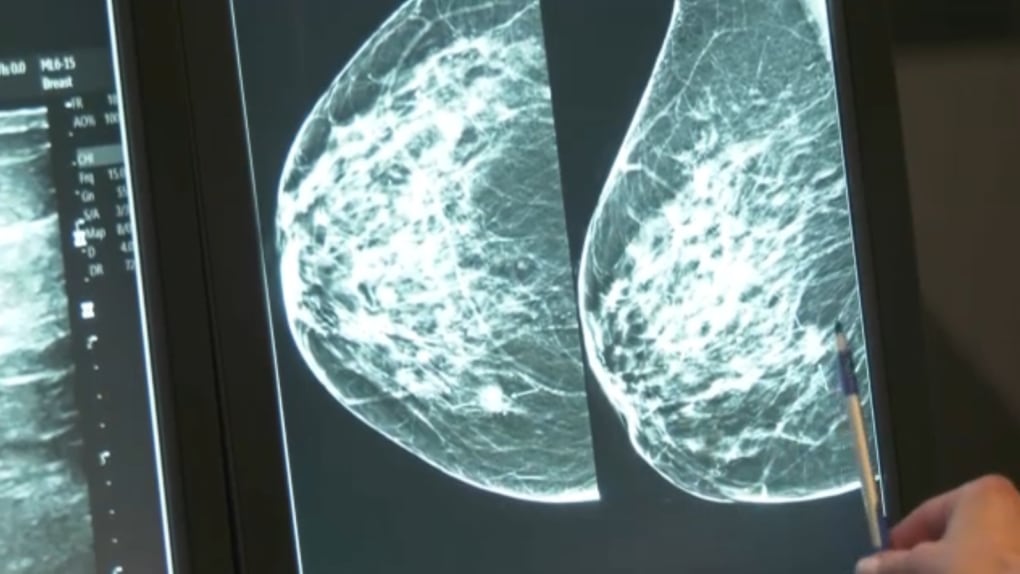

UPDATE: Alberta Health Services is set to launch an urgent mobile mammography service, arriving at Tsuut’ina Nation on November 10, 2023. This critical healthcare initiative aims to enhance access to vital breast cancer screenings for women in the community.

The mobile mammography trailer will be stationed at 5535 37 St SW, Tsuut’ina Nation, offering free screenings to women aged 50 to 74. The service will operate from 9:00 AM to 4:00 PM, providing an essential resource for early detection and prevention of breast cancer.

This initiative is particularly significant as it addresses the healthcare disparities faced by Indigenous communities. Access to regular mammography screenings is crucial; early detection can significantly improve treatment outcomes and save lives.